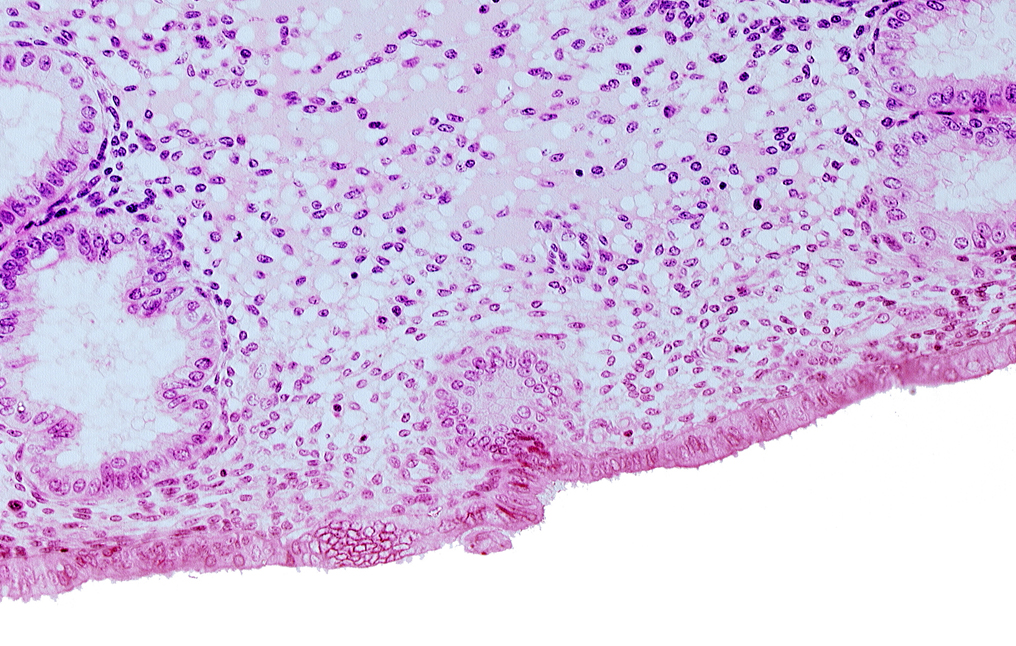

Carnegie Embryo #8020 | Location: 06-06-03

Keywords: disrupted endometrial epithelium, edematous endometrial stroma (decidua), endometrial epithelium, endometrial gland

Source: The Virtual Human Embryo.